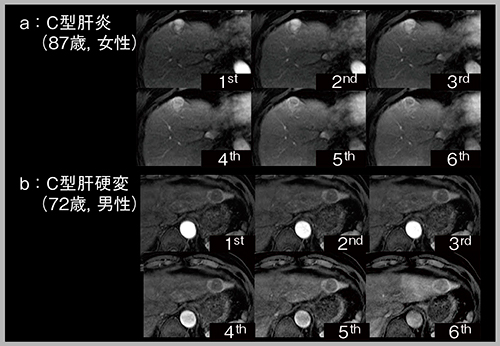

“DISCO”は,view sharingを併用した技術で,k-spaceの中心を頻回に撮像することで多時相化する手法である。DISCOを用いれば,1回の息止めで多数の時相を取得できる。

肝細胞がん(HCC)は動脈相で濃染し,門脈相から遅延相にかけてwash-outするが,その際,辺縁部にリング状の濃染,すなわちenhancing capsuleを呈する。enhancing capsuleは,LI-RADSでは主要項目であり,HCC診断の確信度が向上するとされている。HCCの精査のため当院に紹介された2症例について,DISCOを用いて6相で撮像した動脈相の画像(図4)を見ると,a(87歳,女性,C型肝炎)は最初に全体が濃染し,その後にリング状となる典型的なHCCのパターン,b(72歳,男性,C型肝硬変)は最初からリング状に濃染し,内部が壊死したパターンを呈していた。このように多時相を取得することで,腫瘍の血行動態をより詳細に検討することができる。

図4 View sharing(DISCO)による動脈相の多時相化(HCC精査)